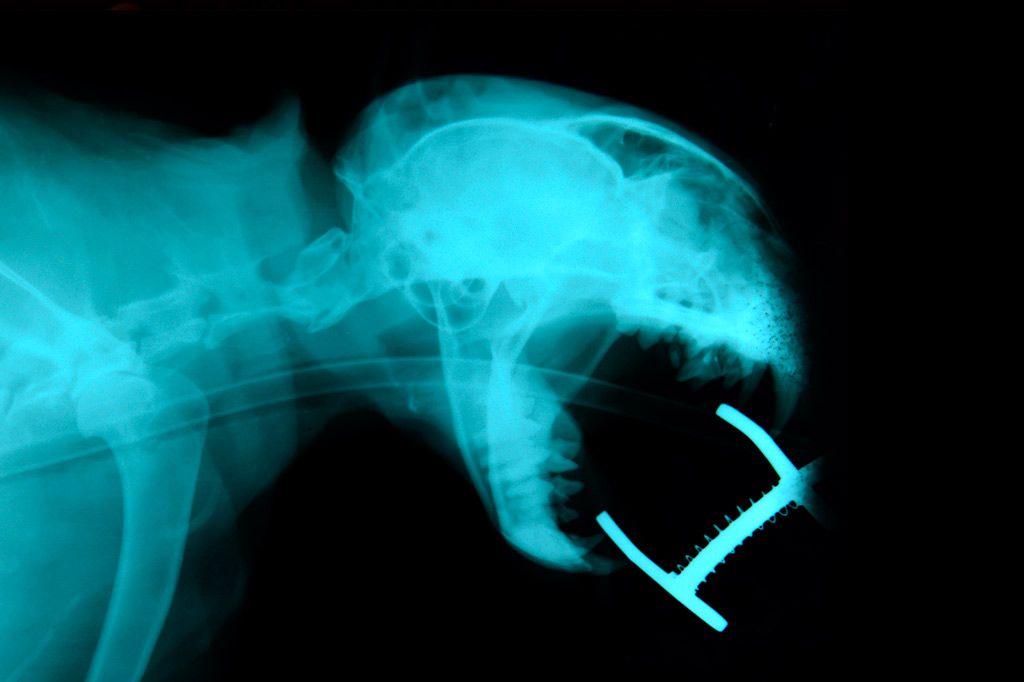

SALUD DENTAL

La boca es parte muy importante del sistema digestivo y su mal estado es causa de muchos problemas gastrointestinales.

Una boca en mal estado es causa de mal olor (halitosis), cosa molesta para sus propietarios y también un foco infeccioso para ellos.

Nosotros le orientaremos en como mantener una salud bucal adecuada. Una de las actuaciones más importantes para mantener una boca sana es la limpieza dental con ultrasonidos para levantar las capas de sarro que se depositan en los dientes.

Nuestro centro cuenta con servicio de limpieza bucal y extracciones dentales.